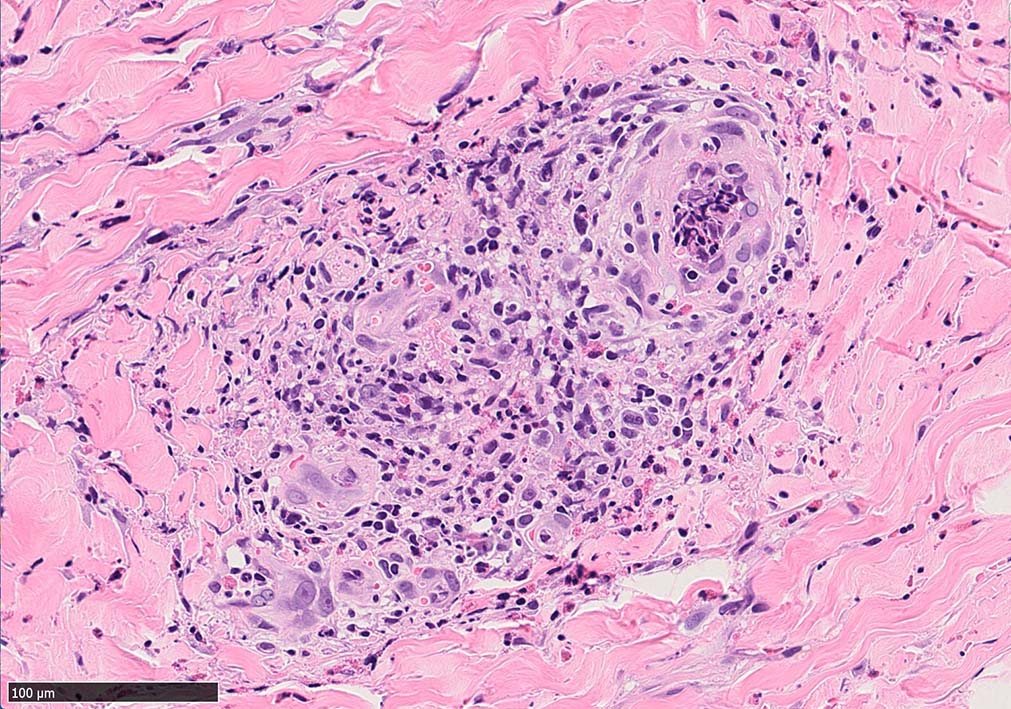

IWT-case03 マダニに咬まれた. 自分で虫体を除去したが傷がびらん化し, 発熱を来したため, 来院する.

痂皮の下に硝子様凝固物があり, 周囲には壊死組織が形成されている. 近傍の細血管には凝固物による閉塞の所見があるように見える. 連続する細血管には, fibrinoid necrosisを呈する壊死性血管炎が認められる.